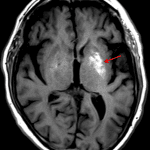

- T1 hyperintensity in the left putamen

- Nonketotic hyperglycemic hemichorea-hemiballism

T1 hyperintensity in the left putamen, which given clinically reported contralateral jerking movements is favored to represent nonketotic hyperglycemic hemichorea-hemiballism. Other toxic/metabolic disorders associated with T1 hyperdensity in the basal ganglia are considered unlikely given profound asymmetry.